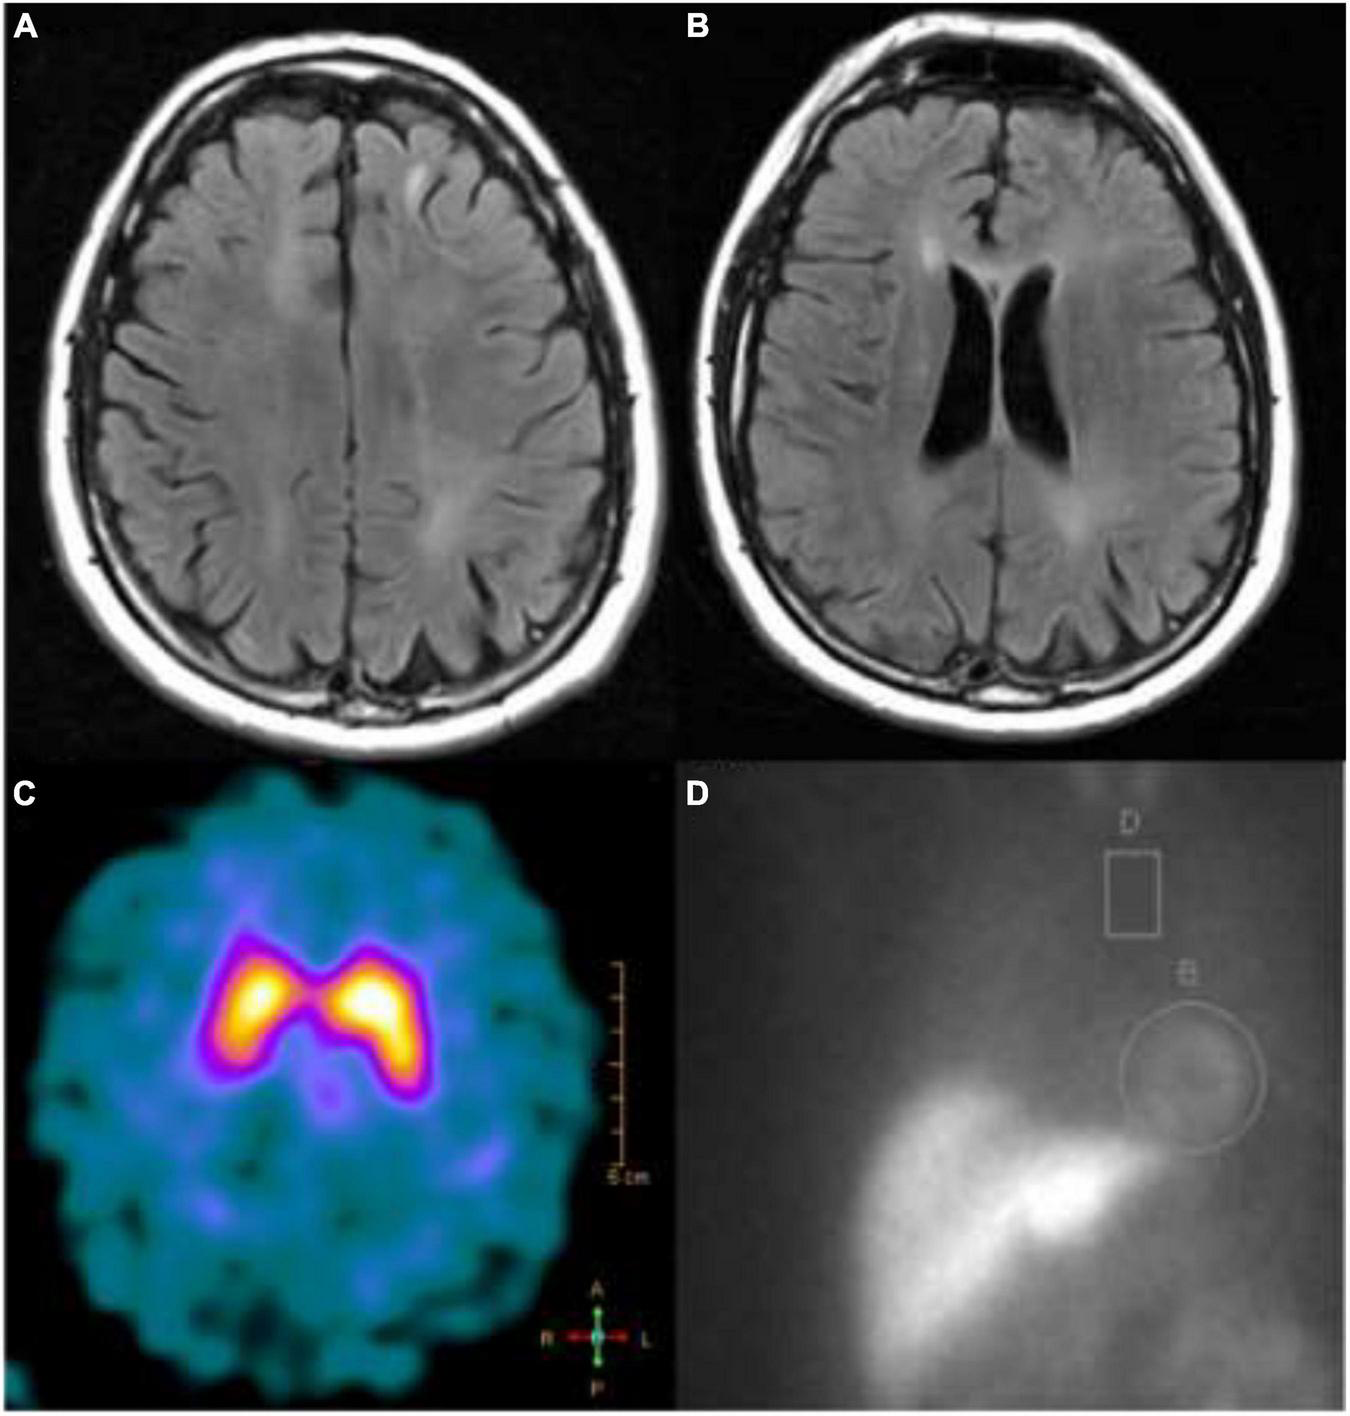

T2-FLAIR MRI showing (A) left frontal juxtacortical hyperintensity and (B) periventricular white matter hyperintensities; (C) a dopamine transporter scan showed reduced tracer uptake in the right putamen; (D) an MIBG scan showing higher than normal (>4:1) heart to mediastinum ratio.

He was treated empirically with high dose steroids (1,200 mg prednisone daily for 5 days consecutively). After steroid treatment, he continued to progress with more ataxia and increasing falls. He was then admitted for additional workup and rehabilitation assessment. A second lumbar puncture was performed (3 months after the first) which again identified 17 OCBs restricted to CSF. A second autoimmune panel from serum and CSF was sent with negative results. He was discharged to a rehab facility without any improvement following his hospitalization. On his return to our clinic, he demonstrated more marked ataxia and new emergence of suspected rapid eye movement behavior disorder (RBD). He was therefore referred to the movement disorder clinic for evaluation of a synucleinopathy. He denied symptomatic orthostasis, but his screening vitals did demonstrate a drop in systolic blood pressure of 32 mmHg. While he did not have pronounced parkinsonism, the cerebellar involvement, autonomic failure, upper motor neuron features, and RBD did suggest a diagnosis of MSA. 123I-Ioflupane single photon emission tomography (SPECT) imaging revealed reduced tracer uptake over the right putamen, indicative of nigrostriatal degeneration (see Figure 2C). Imaging of cardiac innervation with SPECT and [123I]metaiodobenzylguanidine (MIBG; see Figure 2D) demonstrated preserved sympathetic postganglionic neurons.